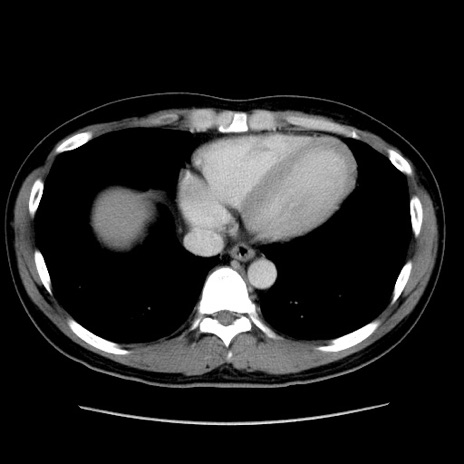

症例4(横断像)

【症例】30歳代男性

【主訴】腹痛、嘔吐

【現病歴】昨晩から突然の腹痛あり、その後嘔吐、軟便も出現。腹痛が改善しないため救急搬送となる。2日前にしめ鯖の食事歴あり。

【身体所見】意識清明、苦悶様、BP 135/90mmHg、BT 35.7℃、腹部:平坦、やや硬、心窩部〜臍部に自発痛、圧痛あり、筋性防御+、反跳痛-

【データ】WBC 8100、CRP 0.57